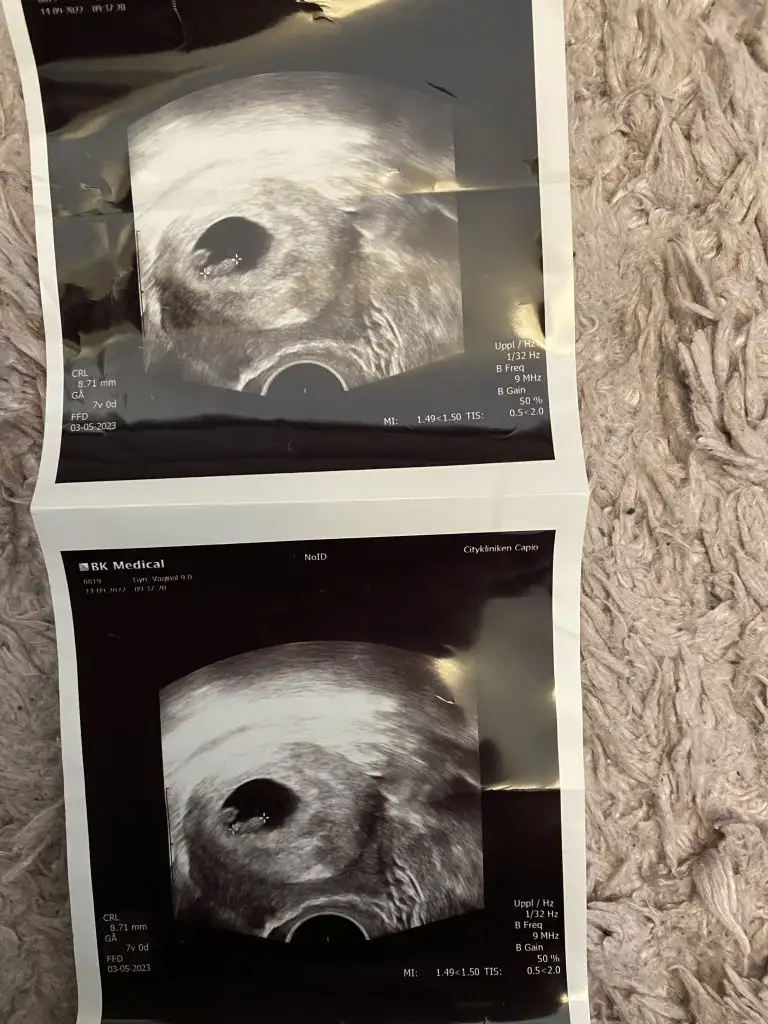

9 haftalik karindan ultrason cinsiyet tahmini yapar misiniz?

Eklentiler

• IMG_20221026_094938.webp

IMG_20221026_094938.webp

24 KB · Görüntüleme: 46

• IMG_20221026_094924.webp

IMG_20221026_094924.webp

21,6 KB · Görüntüleme: 34